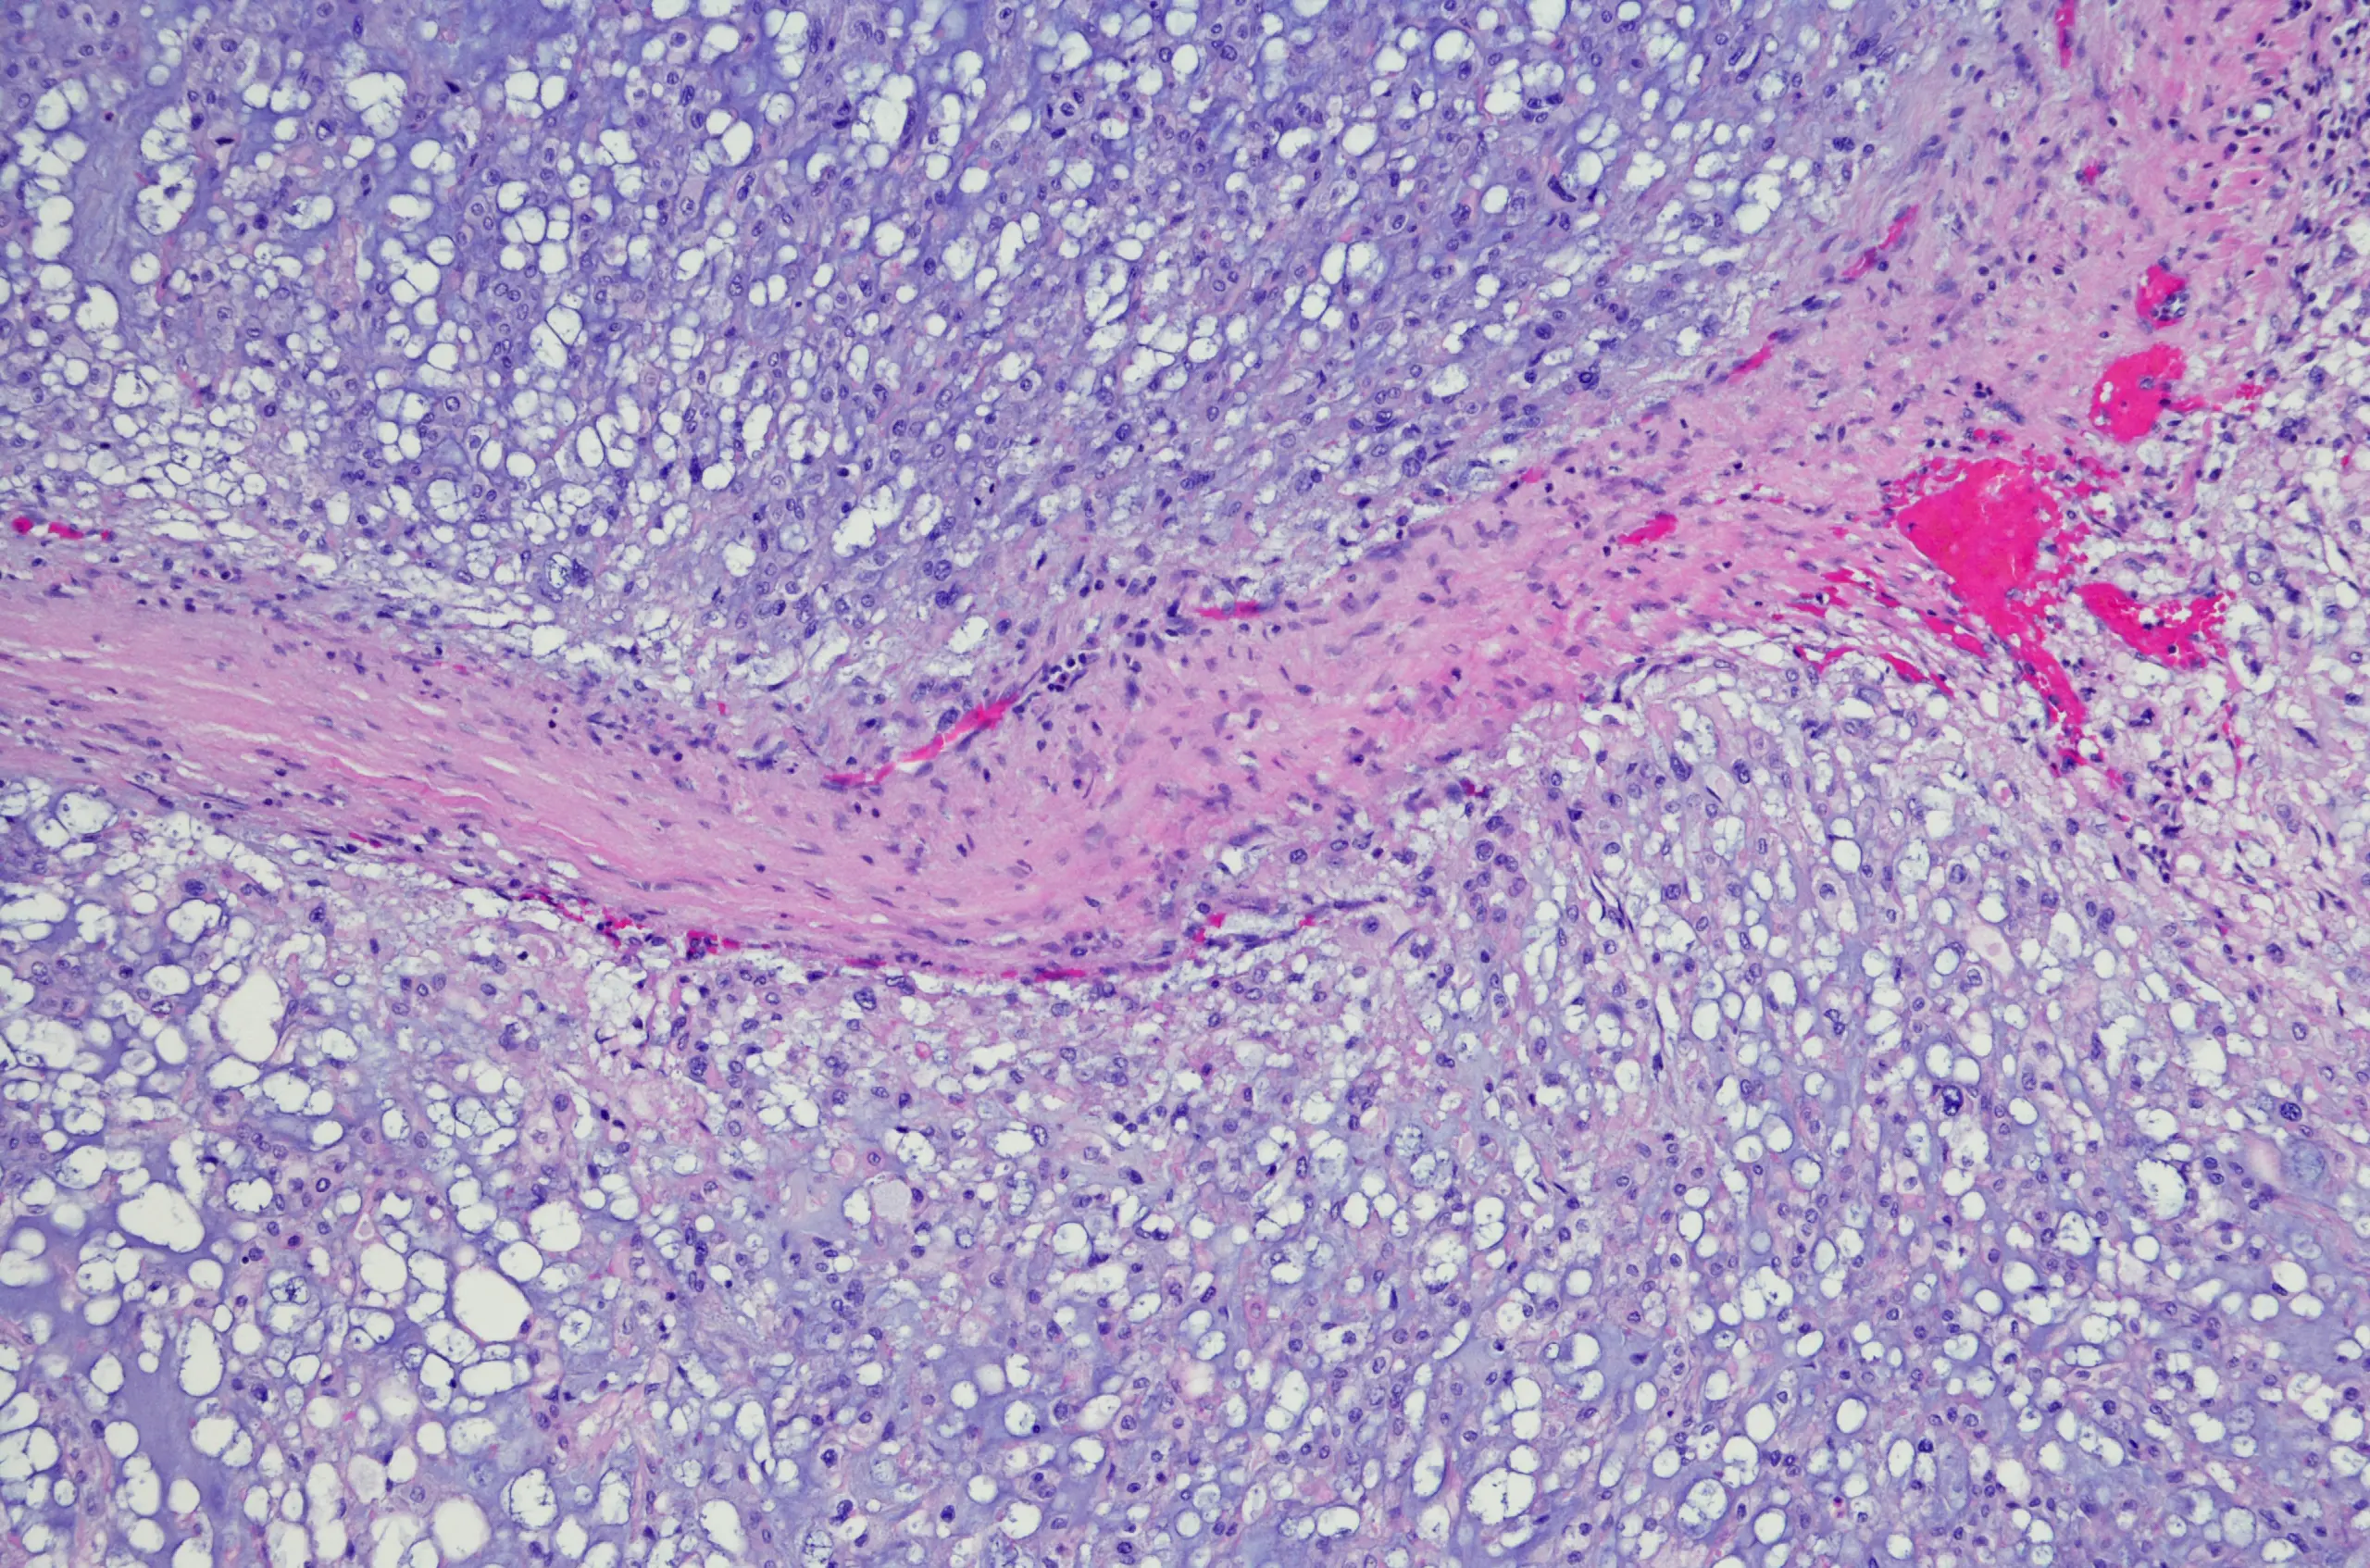

According to Cancer Research UK, chordoma is a rare and slow growing type of primary bone cancer, typically found in either the bottom of the spine or near the base of the skull. Globally, one in 1,000,000 people per year are diagnosed with chordoma.

Current research suggests that chordomas are caused during the development of a baby's spine in the womb in which the notochord, a precursor to the spine, is replaced by bone. However, in some adults notochord cells may remain, which scientists believe cause chordoma.

Put simply, researchers previously found that brachyury is 'essential' to the growth of chordoma tumours and has for years been 'considered undruggable' by scientists.